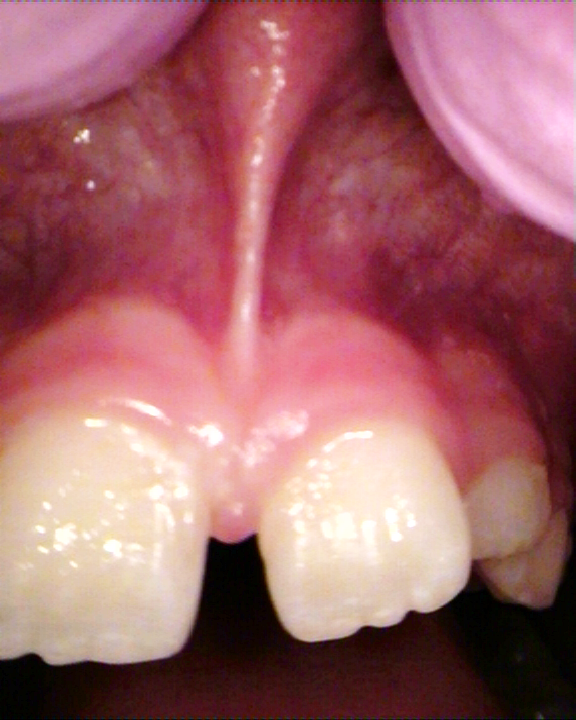

laser stomatologiczny podcięcie wędzidełka